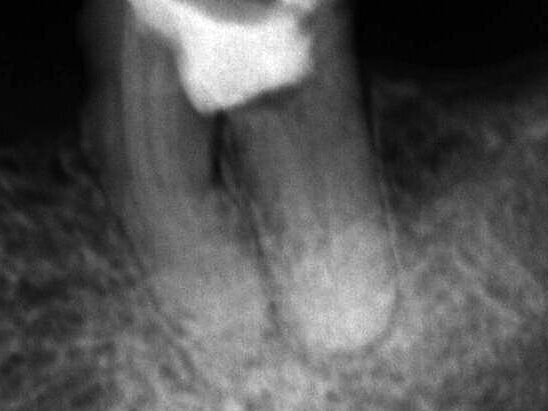

Fig. 3: Obturation of root canals.

The obturation was performed using the thermomechanical Hybrid Tagger technique (Fig. 3), by employing GutaCondensor (Maillefer/Switzerland), TP gutta-percha cones (Dentsply/Brazil) and MTA-based sealer Fillapex (Angelus/Brazil) (Fig. 4). After thermo compaction, the obturation cutting was performed, as well as vertical condensation using cold pusher; and again the region of the perforation was cleaned and filled with Calcium Hydroxide.